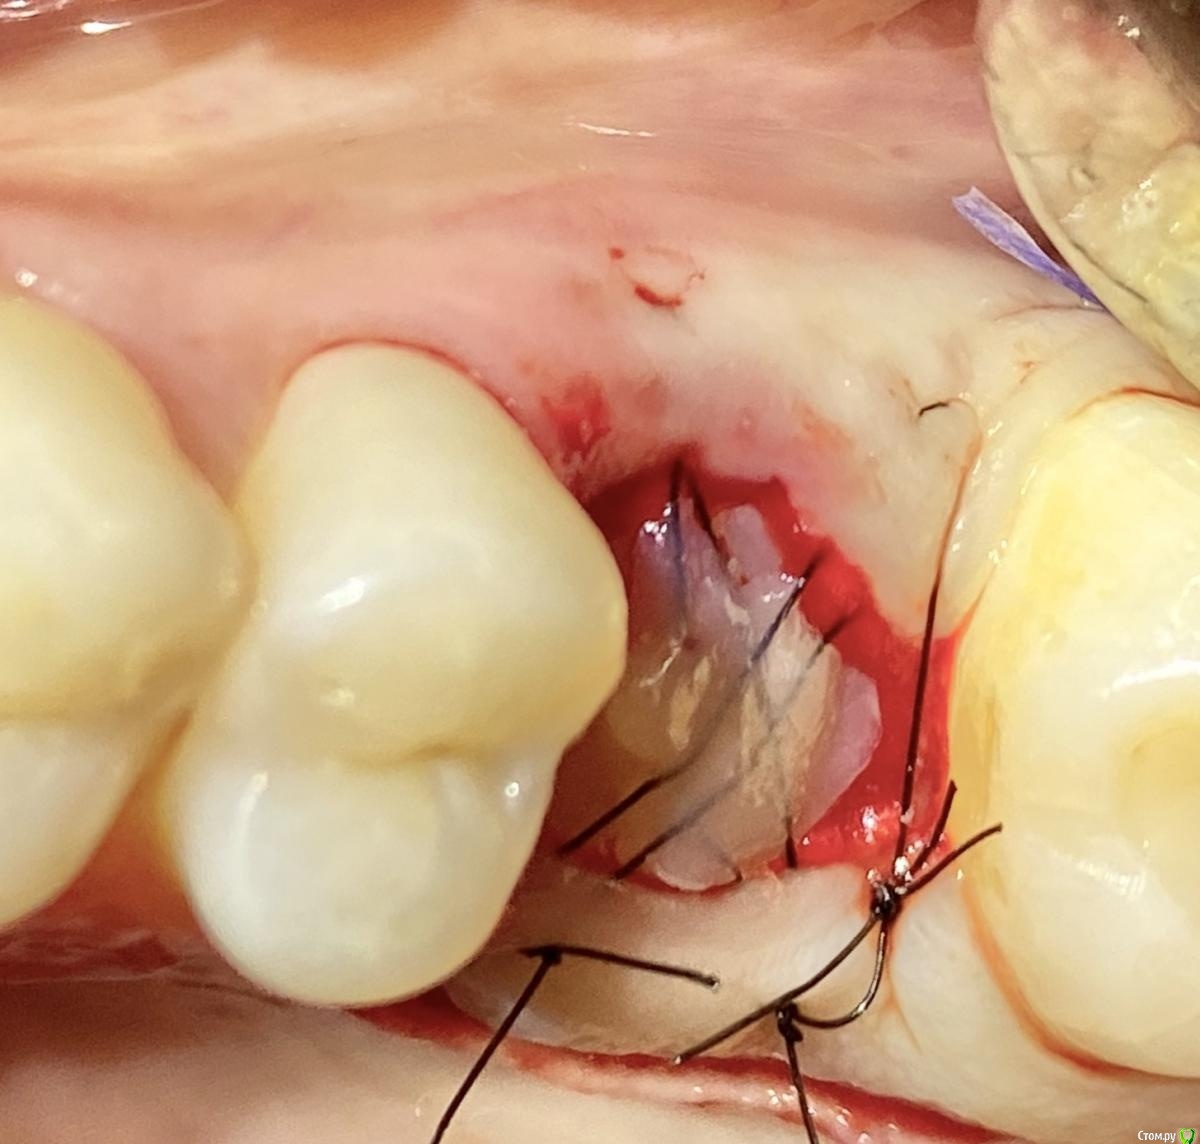

It'sGeorgy Опубликовано 20 февраля, 2021 Поделиться Опубликовано 20 февраля, 2021 А что именно смущает? Что дефект с пазухой сообщается? Так закроете после удаления, ничего страшного. ЛОРу, имхо, там делать нечего пока еще.Недавно был подобный случай: А вообще, судя по тем скринам, которые вы выложили, я бы пациента терапевтам показал для начала. Ссылка на комментарий

It'sGeorgy Опубликовано 20 февраля, 2021 Поделиться Опубликовано 20 февраля, 2021 Именно, что с пазухой. С терапевтами общались, при попытке препарирования зуб "мягкий", как кариозный судя по их словамну так закроете По поводу способа закрытия скажу вообще непопулярное мнение: я бы просто затромбовал колаполом, дал небольшую подвижность вестибулярному лоскуту и сопоставил края монофилом. Знаю, что это не всегда срабатывает, но меня пока проносило, уже раз 20. Дефект, который сверху выкладывал, закрыл таким же способом. Если недостаточно опыта(как у меня и было), возиться с VIP-CT - не лучшая идея. А вообще, не факт, что там будет ОАС. Часто бывает, что между лункой и пазухой есть тонкая костная пластинка, которой просто на снимке не видно. Ссылка на комментарий

Raystom Опубликовано 20 февраля, 2021 Автор Поделиться Опубликовано 20 февраля, 2021 ну так закроете По поводу способа закрытия скажу вообще непопулярное мнение: я бы просто затромбовал колаполом, дал небольшую подвижность вестибулярному лоскуту и сопоставил края монофилом. Знаю, что это не всегда срабатывает, но меня пока проносило, уже раз 20. Дефект, который сверху выкладывал, закрыл таким же способом. Если недостаточно опыта(как у меня и было), возиться с VIP-CT - не лучшая идея. А вообще, не факт, что там будет ОАС. Часто бывает, что между лункой и пазухой есть тонкая костная пластинка, которой просто на снимке не видно.После последней своей темы про оас освоил вип ст, разворот лоскута с бугра Ссылка на комментарий

колесников Опубликовано 24 февраля, 2021 Поделиться Опубликовано 24 февраля, 2021 Консервацию лунки графтом. Колапол хорошо,но только как прокладку под купол. И конечно вестибулярный лоскут не трогать(не мобилизовать) Ссылка на комментарий

колесников Опубликовано 25 февраля, 2021 Поделиться Опубликовано 25 февраля, 2021 Киста сделала синуслифтинг,этот объём надо сохранить,колапол резорбируется быстро и через 3-6 мес останется 3мм,графт не скиснет,а созреет по форме дефекта,надо избежать вторичного инфицирования. Перекрыть вестибулярным лоскутом лунку не получится,раскрытие-инфицирование,боль,отёк,контрактура,смешение биотипа. Зачем? Можно нёбный мобилизовать или выбрать другой способ герметичного закрытия лунки Ссылка на комментарий